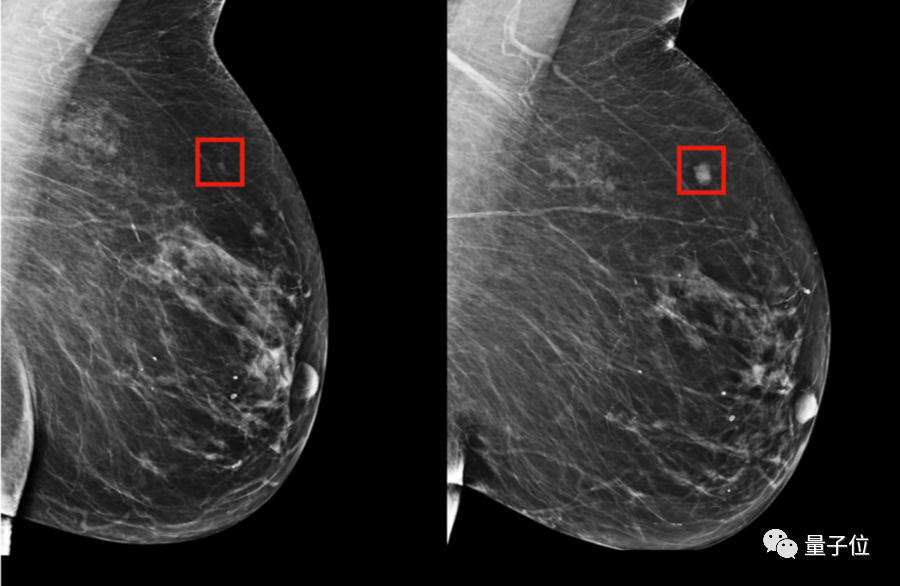

最值得一提的,就是她研发的早期乳腺癌诊断预警模型。

现在,她的这项研究——使用AI算法来判断癌症风险,已经投入临床了。

而针对TC模型的不足,Barzilay博士和她的团队开发了三种不同的模型。

一种是基于传统风险因素进行判断的逻辑回归模型(RF-LR);将患者在进行乳房X光检查时的风险因素映射到患者在5年内是否患癌这个结果上。

第二个是仅基于X光片图像的深度学习模型;用PyTorch构建了一个深度卷积神经网络ResNet。给定一个乳房的1664 X 2048像素图片,模型会预测是否会在5年内发展成乳腺癌。

最后一种是结合RF-LR和X光片的混合模型,这也是最终投入临床使用,准确率最高的模型。

在临床对比中,在已确诊的乳腺癌患者中,混合模型在前期就对其中的31%作出了预警,而传统的TC模型的有效预警仅有18%